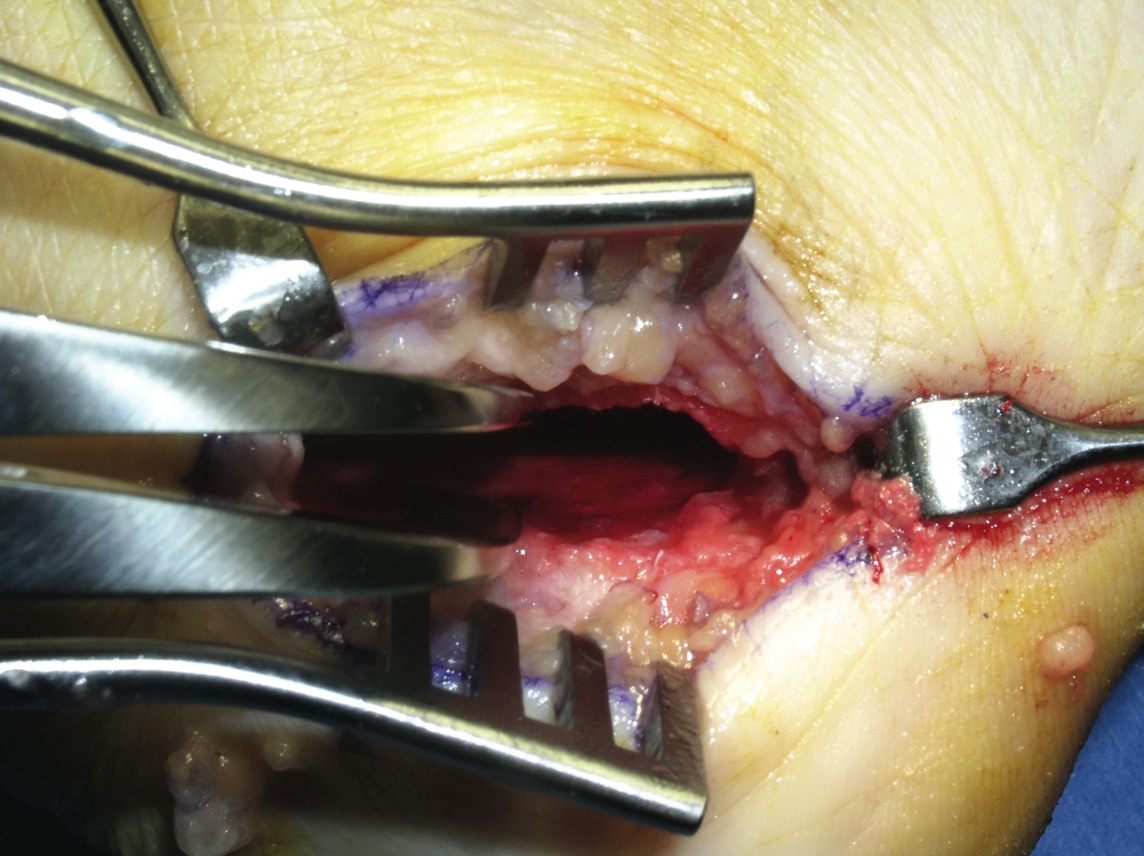

Adult-acquired flatfoot (AAF) is one of the more common conditions that podiatrists see in practice. With this in mind, some of the leading experts on this subject shared their views and experience on this subject. They discuss the role of diagnostic imaging, their use of conservative treatments and their perspectives on appropriate surgical procedures. Without further delay, here is what they had to say. Q: What ancillary studies are required for proper diagnosis and treatment selection for the adult-acquired flatfoot? A: Michael S. Lee, DPM, says AAF is generally a clinical diagnosis. Other than the physical exam, Shannon Rush, DPM, says a proper radiographic evaluation is the most important aspect of diagnosing AAF and arriving at an appropriate course of treatment. Dr. Rush emphasizes the inclusion of foot and ankle views as well as hindfoot alignment and long leg calcaneal views. All the panelists agree that neutral position X-rays are helpful in determining the degree of the deformity and what procedure one should perform. Alan Catanzariti, DPM, says it is important to evaluate the talus-first metatarsal angle on both AP and lateral radiographs. He adds that the AP views also enable one to see the amount of talar head that is covered by the navicular. Standard radiographs also allow clinicians to assess the tritarsal complex for degenerative changes, according to Dr. Catanzariti. He says these degenerative changes may indicate an arthrodesis procedure as opposed to performing reconstructive osteotomies or soft tissue procedures. The majority of the panelists recommend obtaining ankle X-rays in order to detect valgus deformity within the ankle. When there is valgus deformity within the ankle joint, Dr. Catanzariti will typically consider performing a medial displacement osteotomy of the calcaneus. “This helps decrease the tension within the deltoid ligament and prevent further attenuation of medial soft tissue structures,” explains Dr. Catanzariti. In cases of end-stage flatfoot deformity, Jordan Grossman, DPM, says AP ankle views are useful in evaluating for deltoid ligament insufficiency and valgus deformity of the talus within the ankle mortise. Gerard V. Yu, DPM, and Dr. Catanzariti agree with Dr. Rush about the value of obtaining long leg axial films. Dr. Catanzariti says long leg axial views and Saltzman views allow one to evaluate the calcaneus, subtalar joint, ankle joint and tibia relative to one another. He adds that these views often facilitate appropriate procedure selection. Lower-extremity alignment views may also be indicated in certain instances, according to Dr. Rush. Dr. Grossman concurs, noting that obtaining Cobey and hindfoot alignment views are useful in severe cases and with lower-extremity deformity. When it comes to magnetic resonance imaging (MRI), Dr. Rush says he “rarely, if ever” uses it in his workup for AAF. Dr. Catanzariti agrees. However, if he is contemplating arthrodesis versus reconstruction, Dr. Catanzariti will sometimes obtain a MRI in order to detect early degenerative changes within the subtalar joint that are subtle on standard X-rays. Dr. Grossman concurs, noting that MRI is indicated in “select circumstances” in which the diagnosis is unclear. Dr. Lee says one may employ MRI or ultrasound imaging to evaluate the posterior tibial tendon for attenuation or complete rupture. Dr. Yu emphasizes that MRI is most helpful when clinicians use a facility that has an experienced musculoskeletal radiologist, who is knowledgeable about the clinical entity and its primary and secondary manifestations. “I believe the MRI should be part of the standard workup for AAF if you plan to do direct surgical repair alone or as part of the correction of the deformity,” maintains Dr. Yu. Dr. Lee adds that a CT scan may have limited use in determining the degree of arthrosis in stage 3 or stage 4 deformities. Gait analysis may also be helpful in procedure selection, according to Dr. Catanzariti. Q: What is the significance of the posterior tibial tendon in the adult-acquired flatfoot? A: Dr. Yu says the primary purpose of the posterior tibial tendon is decelerating internal rotation of the tibia and accordingly limiting pronation of the foot following heel strike in gait. The intrinsic pathology specific to the posterior tibial tendon is “insignificant once the deformity has occurred,” notes Dr. Rush. He says the most important overriding factor is that the tendon has functionally weakened and is unable to stabilize the midtarsal joint. Dr. Rush says this functional weakness may be due to posterior tibial tendon dysfunction (PTTD) or subluxation in the rearfoot. The posterior tibial tendon plays “a primary role in the development of AAF,” according to Dr. Grossman. Dr. Lee says the posterior tibial tendon plays an important role early in the process but its importance diminishes as the deformity progresses. He notes the spring ligament may become attenuated in some situations. While there are several possible causes of AAF, Dr. Grossman says insufficiency or rupture of the posterior tibial tendon is the most common cause. The posterior tibial tendon often may be attenuated or diseased in AAF, according to Dr. Catanzariti, but he says this can vary from patient to patient. If patients have significant symptoms as a direct result of disease within the posterior tibial tendon, Dr. Catanzariti says they may require surgical intervention, which could include a tenosynovectomy, a partial tendon debridement or actual resection of an attenuated tendon. He notes these interventions may be supported by tendon transfers. In these cases, Dr. Catanzariti prefers a flexor digitorum longus tendon transfer. Dr. Rush says the clinical view of the posterior tibial tendon or its appearance on MRI does not influence one particular reconstruction over another. When it comes to stage 3 and stage 4 AAF, Dr. Lee says the posterior tibial tendon plays little importance in function, diagnosis or surgical treatment selection. If a patient has a predisposition to excessive pronation due to a specific foot structure, Dr. Yu says the posterior tibial tendon is “very significant.” When patients have a cavus foot, he notes the inherent stability of the foot will limit pronation. However, if a patient has hypermobile joint laxity syndrome, Dr. Yu says the posterior tibial tendon will be more important as it will “work harder to prevent excessive pronation.” If one stabilizes the foot well with osseous procedures, especially fusions, the importance of the posterior tibial tendon for function decreases, according to Dr. Yu. When one performs a posterior tibial tendon transfer for other conditions (i.e., dropfoot deformity), Dr. Yu says the foot structure remains the same due to the inherent interlocking of osseous units. When performing a triple arthrodesis, Dr. Yu notes the surgeon can leave the PT tendon alone altogether unless the pain there is due to active inflammation around the tendon itself. In essence, the more inherently stable the foot is, whether by surgical fusion or anatomical stability, the less important the PT tendon is to overall foot function. Q: What conservative measures have been successful in your hands in the treatment of AAF? A: Employing orthotics in combination with antiinflammatory medications and posterior muscle group stretching provides relief in milder cases of AAF, according to Dr. Catanzariti. When it comes to stage 1 conditions, Dr. Lee notes he has had a fair amount of success utilizing figure-of-eight ankle braces along with rest, ice, NSAIDs and shoe gear modifications. He notes that stage 2 deformities have responded well to prefabricated and custom orthotics, rest, activity modification and NSAIDs. Dr. Lee has also utilized ankle foot orthoses (AFOs). Depending on the presentation and degree of the deformity, Dr. Grossman says he has had success with the aforementioned modalities as well as physical therapy, cast immobilization and a removable walking boot. Functional orthotics may be helpful in the early stage of AAF but Dr. Yu says he generally does not use them. Dr. Yu notes that some companies make a variety of orthotic devices that “are too flimsy and do not have enough substance to do the job.” Essentially, one needs to ensure bracing of the foot to the leg, according to Dr. Yu, especially in the presence of other factors like obesity, genu valgum, etc. Dr. Yu says Aircast ankle braces and similar devices may provide good relief prior to using the more sophisticated and expensive devices like the Richie Brace and AFOs. With chronic conditions, Dr. Rush will use aggressive custom orthoses, Richie Braces and the Arizona AFO prior to surgical intervention. With stage 3 and stage 4 deformities, Dr. Lee will brace them with either UCBL orthotics or AFOs. If these fail, he proceeds to surgical intervention. The other panelists concur that one can use conservative bracing for stage 3 and stage 4 deformities in patients who are not surgical candidates. In these patients, Dr. Rush has had success with the Arizona AFO while Dr. Catanzariti has utilized supramalleolar AFOs with good results. In regard to conservative therapy, Drs. Rush and Yu say there are many factors to consider including the patient’s level of activity, weight loss, patient education, proper shoe gear and rehabilitation. Realistic expectations are essential and become more important as patients progress from stages 1 to 4, according to Dr. Yu. He says a patient with stage 3 or 4 deformity and low activity may respond surprisingly well to bracing but bracing is unlikely to be successful in a highly active patient with stage 2 AAF. Q: At what point does AAF become a surgical foot? A: The majority of the panelists consider surgical treatment when the deformity is progressive, grossly unstable and doesn’t respond to functional bracing. Dr. Rush says the potential progression of the deformity is a significant concern. “Severe talonavicular and subtalar subluxation can have a devastating influence on the ankle joint,” emphasizes Dr. Rush. “If the lateral peritalar drift is left unabated, the ankle can also fall into valgus.” Dr. Lee says he performs surgery for end-stage deformities such as stage 3 and stage 4 conditions. However, Dr. Yu notes that even severe deformities do not justify surgery alone. “If the other foot is flat and asyptomatic, you may be able to manage the pathologic foot without surgery,” points out Dr. Yu. If bracing fails, one needs to turn to surgical options, according to Dr. Yu. He emphasizes that physicians should always remember to treat patients in conjunction with their disease or deformity and not the X-rays. He notes that clinical correlation is essential to effective treatment. Q: When are calcaneal osteotomies indicated in the treatment of AAF? A: Dr. Yu says these procedures are “rarely” indicated for treating AAF. He believes this approach has been abused in an attempt to avoid more time-tested techniques, such as the gold standard triple arthrodesis, especially in the later stages of AAF when the deformity can be quite severe. In his experience, Dr. Yu says the calcaneal osteotomy has little impact in resolving severe AAF “when a fusion in conjunction with tibialis posterior repair and posterior lengthening would have worked out better.” While he notes that calcaneal osteotomies are very helpful in the earlier stages of the disease, Dr. Yu emphasizes that many of these patients will do well without surgery. Drs. Grossman, Catanzariti and Lee believe calcaneal osteotomies are primarily indicated for flexible or reducible deformities. These procedures allow surgeons to correct various deformities while maintaining midtarsal and subtalar joint motion, according to Dr. Grossman. He says this will “most likely decrease the likelihood of adjacent joint demand and arthrosis that one commonly sees with an isolated or triple arthrodesis.” Citing the versatility of calcaneal osteotomies, Dr. Catanzariti calls them an excellent alternative to arthrodesis procedures. “These osteotomies spare the tritarsal complex and allow the hindfoot to function in a relatively normal fashion,” explains Dr. Catanzariti. Dr. Lee concurs. If the flatfoot is supple, he says one can achieve correction with calcaneal osteotomies while preserving most of the hindfoot motion. When it comes to late stage 1 AAF, Dr. Catanzariti will consider posterior calcaneal displacement osteotomies and sometimes uses this approach to treat early stage 2 conditions. Dr. Lee utilizes posterior calcaneal displacement osteotomies for early stage 2 AAF and employs the Evans calcaneal osteotomy and double osteotomies for late stage 2 conditions. For mid- to late stage 2 AAF, Dr. Catanzariti considers performing an anterior open wedge osteotomy in combination with a posterior displacement osteotomy. Dr. Rush says calcaneal osteotomies are a “wonderful surgical tool” for treating AAF. He performs a posterior osteotomy with any valgus malalignment of the subtalar joint when a subtalar arthrodesis is not indicated. Obtaining hindfoot alignment and long leg calcaneal axial views help in planning with this procedure, according to Dr. Rush. He maintains that clinicians must be careful to evaluate the midtarsal joint and medial column for instability and supinatus. In the presence of instability or deformity, Dr. Rush notes one must add ancillary procedures in order to stabilize the medial column. Dr. Rush adds that naviculocuneiform arthrodeses serve to stabilize the medial column and address the naviculocuneiform fault if one exists. Dr. Grossman says he typically performs calcaneal osteotomies in combination with other bony and/or soft tissue procedures. Dr. Rush does not utilize an isolated anterior calcaneal osteotomy for AAF. He says one must combine this procedure with the posterior osteotomy to correct the valgus and lateral translation in the subtalar joint. Dr. Rush strongly emphasizes paying close attention to the subtalar alignment when selecting these procedures. Dr. Lee also notes that he prefers calcaneal osteotomies over isolated hindfoot fusions when treating AAF in smokers, more active patients and those with a normal or slightly elevated body mass index (BMI). Q: When is an isolated or combined joint arthrodesis indicated in treating AAF? A: According to Dr. Yu, these procedures are indicated when there is significant deformity with significant disability and symptoms, especially in cases that involve degenerative arthritis or excessive mobility that cannot be predictably controlled by other means. When one considers performing three joint preservation procedures, Dr. Yu believes one joint fusion can achieve the same outcome. He says performing an isolated joint fusion is especially beneficial for patients who have a low level of activity and want relief of their pain and a stable foot. If one achieves the fusion in a neutral position without varus or valgus, Dr. Yu says the fusion provides “exceptional functional outcomes” with minimal stress on adjacent joints, which minimizes the risk of subsequent degenerative joint disease. “It’s all about the alignment and position of fusion,” emphasizes Dr. Yu. Over the years, Dr. Yu notes anecdotally that he has observed, examined and analyzed a large number of adult patients who had congenital coalitions, realizing they had minimal to no symptoms until their late 40s and 50s or even later. Dr. Yu says the position of the fusion is key to minimizing stress on adjacent joints and structures. Tarsal coalition patients who present early in life invariably have peroneal spastic flatfoot deformities, creating a completely different clinical problem, according to Dr. Yu. However, he emphasizes that the technique one uses to perform these fusions is important. Rigid deformities, a degenerative midtarsal or subtalar arthritis are the primary indications for using isolated or combined arthrodesis procedures, according to Dr. Grossman. He says one may also consider these procedures for obese patients with AAF or in cases of underlying inflammatory arthritis. Dr. Grossman says he typically combines an isolated arthrodesis procedure with soft tissue reconstruction and posterior muscle group lengthening. As with all arthrodesis procedures, Dr. Grossman says the position primarily predicates outcomes and patient satisfaction. Dr. Lee utilizes isolated hindfoot fusions in late stage 2 deformities when there may be mild arthrosis in one or more of the hindfoot joints, when the deformity is severe on plain radiographs or in patients with a higher BMI. A subtalar joint arthrodesis may be effective in the presence of isolated subtalar joint disease or arthritis, according to Dr. Catanzariti, but he rarely uses this procedure to treat AAF. In these cases, Dr. Catanzariti prefers a double calcaneal osteotomy for stage 2 AAF, a triple arthrodesis for stage 3 AAF and a combination of triple arthrodesis and posterior calcaneal displacement osteotomy for stage 4 AAF. On the other hand, Dr. Lee says he tends to perform an isolated subtalar joint arthrodesis in many cases of AAF but will occasionally opt for talonavicular arthrodesis in more severe cases of AAF with significant talar declination. Dr. Rush notes that painful degenerative joints and significant subluxation in the subtalar or talonavicular joints are general indications for arthrodesis. Arthrodesis of the non-essential medial column joints, such as the naviculocuneiform or metatarsocuneiform joints, can easily and effectively stabilize the medial arch, according to Dr. Rush. He adds that combining this procedure with calcaneal osteotomies can “correct most degrees of instability.” While distraction fusions are effective for lateral peritalar subluxation, Dr. Rush cautions that they often do not address the valgus or translation in the subtalar joint. According to Dr. Lee, distraction arthrodesis of the calcaneocuboid joint is a powerful procedure but does have “some elevated risk of non-union.” In the presence of supinatus or varus deformities, all the panelists agree that one must perform some type of ancillary medial column procedure, whether it is a medial column fusion or an osteotomy. Dr. Mendicino is Chief of the Division of Foot and Ankle Surgery at the Western Pennsylvania Hospital in Pittsburgh. He is a Fellow and Past President of the American College of Foot and Ankle Surgeons, and is a Clinical Professor of Surgery at the Western Campus of the Temple University School of Medicine. Dr. Catanzariti is the Director of the Residency Training Program within the Division of Foot and Ankle Surgery at the Western Pennsylvania Hospital in Pittsburgh. He is a Fellow of the American College of Foot and Ankle Surgeons. Dr. Grossman is Chief of the Section of Podiatry at Akron General Medical Center in Ohio. He is a Fellow of the American College of Foot and Ankle Surgeons, and a Diplomate of the American Board of Podiatric Surgery. Dr. Lee is a Fellow and serves on the Board of Directors of the American College of Foot and Ankle Surgeons. He is a Diplomate of the American Board of Podiatric Surgeons. He recently chaired the adult flatfoot panel and co-authored the ACFAS Clinical Practice Guidelines for Adult Flatfoot. He is in private practice at Central Iowa Orthopedics in Des Moines, Iowa. Dr. Rush is a Fellow of the American College of Foot and Ankle Surgeons. He is a Staff Surgeon within the Department of Orthopedics at Kaiser Permanente in Walnut Creek, Ca. Dr. Rush is also a Staff Surgeon with the San Francisco Bay Area Foot and Ankle Residency Program. Dr. Yu is the Director of the Podiatric Surgical Residency Program (PSR-36) and is the Chief of the Section of Podiatry of the Division of Orthopedic Surgery at the St. Vincent Charity Hospital, and at the Huron Hospital in Cleveland. He is a Fellow of the American College of Foot and Ankle Surgeons, and is a Diplomate of the American Board of Podiatric Surgery. Dr. Yu is also the Director of Program Development and a faculty member of the Podiatry Institute.